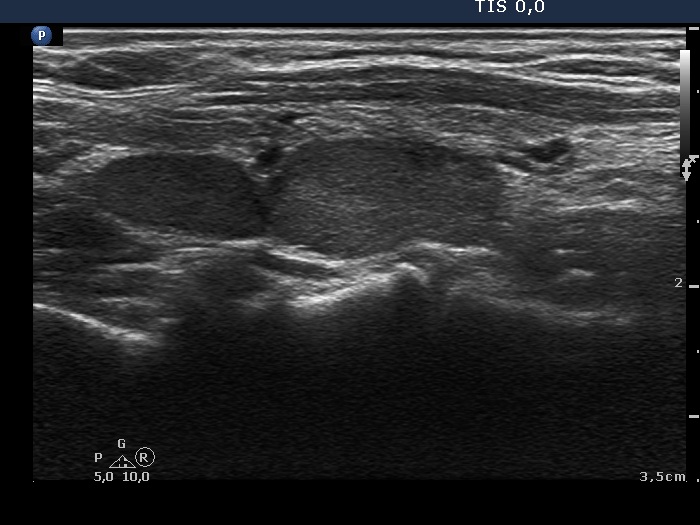

Follow-up examination 3 years later (second row of images):

Clinical presentation: the patient had no complaints.

Palpation: Both lobes were firm.

Laboratory tests: TSH 2.61 mIU/L on daily 125 microgram levothyroxine.

Ultrasonography: The thyroid was unchanged. The lesions in the dorsal part of the right lobe increased in size and a small hypoechogenic area appeared in the ventral part of the left lobe.

Aspiration cytology was performed from the lesion in the dorsal part of the thyroid. We gained only scattered number of epithelial cells without any atypia.

Wash-out thyroglobulin and parathormone levels were determined, the former was 74.4 ng/mL while the latter was above 474 pg/mL.

A repeat blood test was performed. Serum thyroglobulin resulted in 11.9 ng/mL while serum parathormone level did in 180.7 pg/mL. Serum calcium was 2.94 mM/L, serum phosphorus 0.69 mM/L.

Scintigraphy disclosed parathyroid enlargement not only in the right but even in the left side.

Surgery was performed. Histopathology disclosed hyperplasia of all four parathyroids.